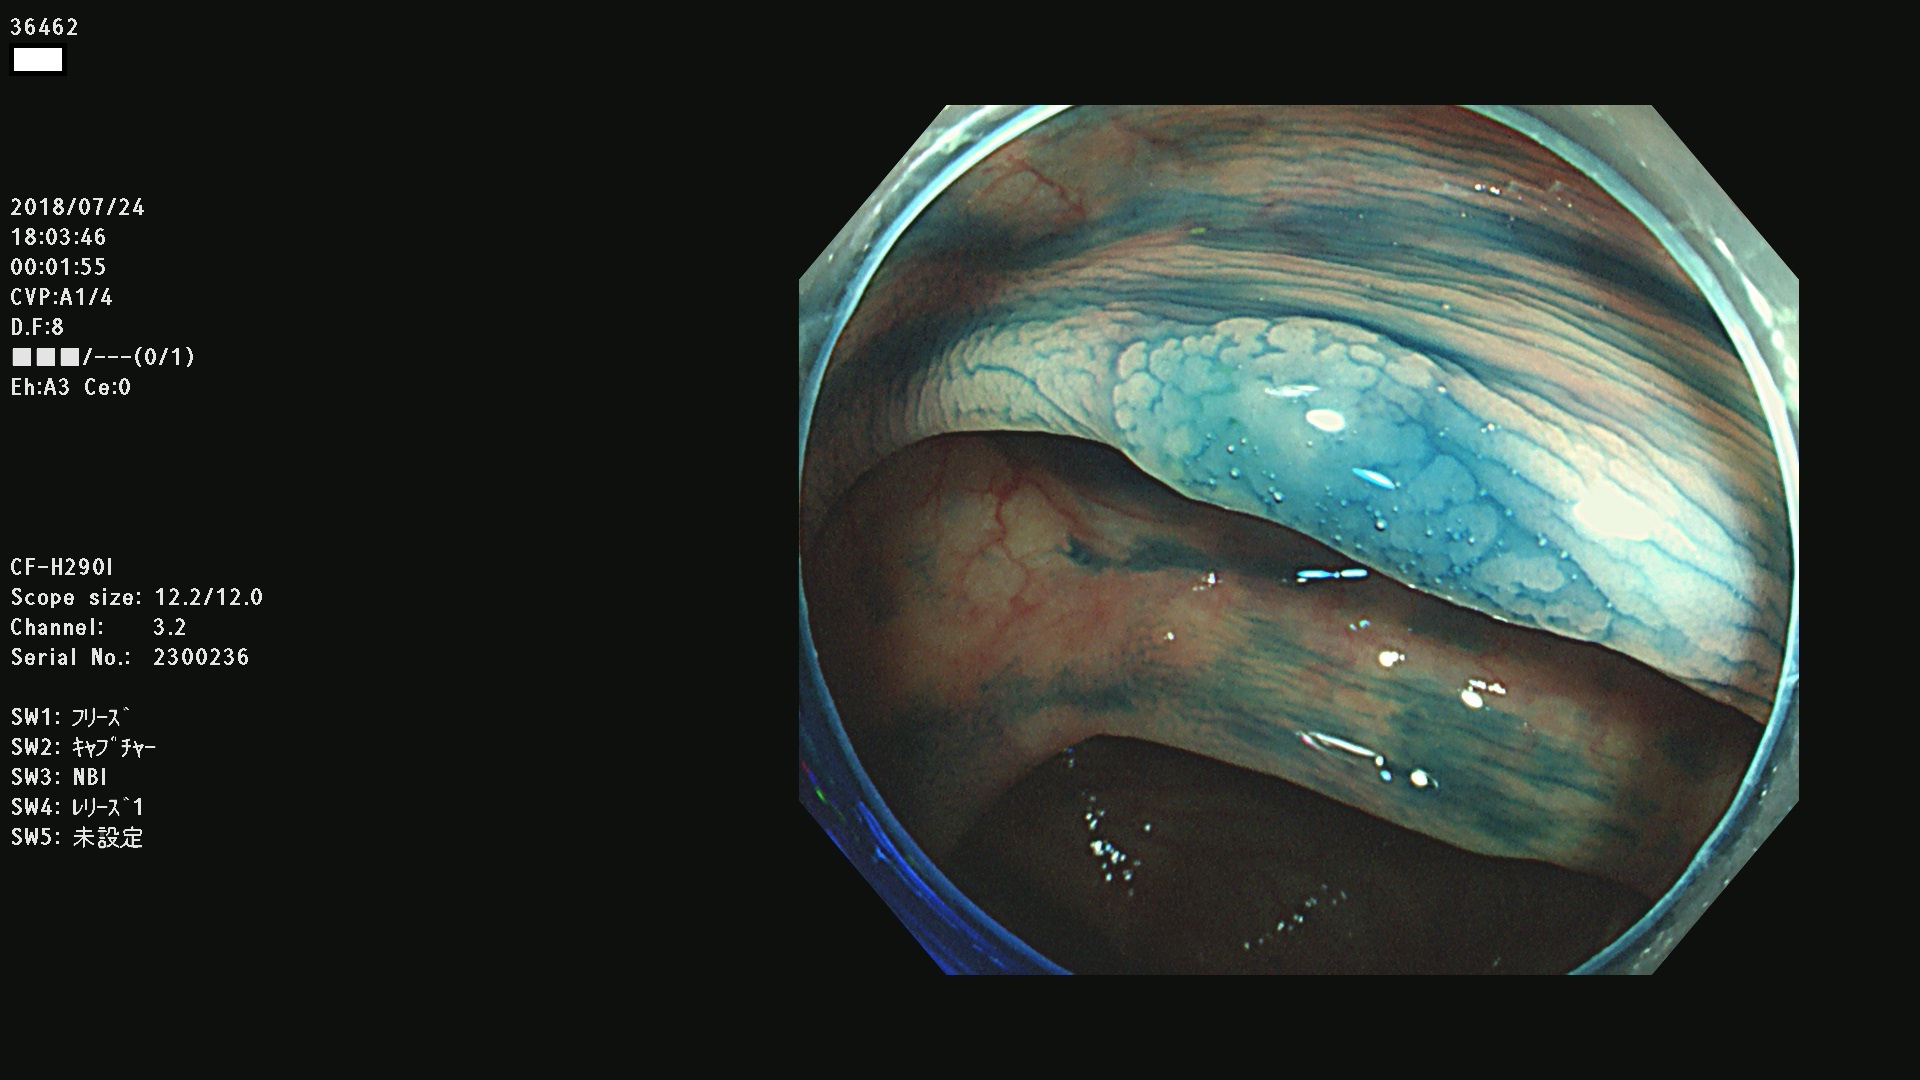

36400(SSAPのみ) 36402 36403 36404 36405 36406 36407 36408(SSAPのみ) 36412 36413 36414 36415 36416 36417 36418 36420 36422 36423 36424 36425 36426 36428 36429 36430 36431 36434 36435 36436 36437 36438 36440 36443 36447 36448 36449 36450 36452 36454 36458 36459 36460 36462(SSAPのみ) 36463 36464 36465 36466 36470 36471 36472 36473 36474 36475 36476 36478 36480 36481 36482 36484 36487 36488 36489 36490 36492 36494 36495 36496 36497 36498

発見困難で危険性の高い平坦型病変(上記100名より抽出)